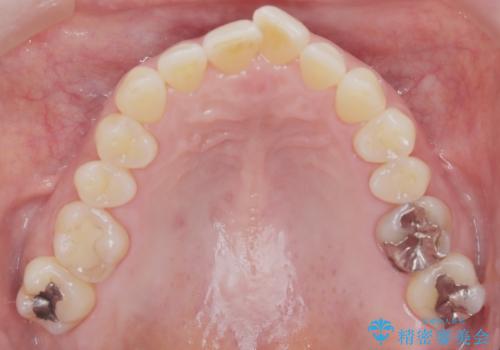

前歯の軽度なガタつきを、1年で美しく整える審美ワイヤー矯正

- 前歯の軽度なガタつき(叢生)を気にされてご来院されました。精密な検査の結果、抜歯は不要で、わずかなスペースを確保することで歯並びを整えられると診断。患者様のご希望と状態に合わせ、目立ちにくい審美ブラケットを使用したワイヤー矯正による治療計画を立案しました。スペース確保は、奥歯を少し後ろへ動かす遠心移動と、歯の側面をわずかに削る**IPR(歯間乳頭保護下ストリッピング)**を併用し、約1年間での治療完了を目指しました。

今回の矯正治療では、歯の色に近い目立たない審美ブラケットとワイヤーを使用しました。

スペース確保のために、まず奥歯全体をわずかに後方へ動かす遠心移動を実施し、前歯を並べるためのスペースを確保。さらに、安全性に配慮しながら歯の側面をわずかに削るIPRを併用し、デコボコを解消しました。

ワイヤー矯正ならではの確実な歯のコントロールにより、当初の計画通り約1年という短い期間で、前歯のガタつきが解消。見た目が美しく整っただけでなく、清掃しやすい機能的な歯並びを獲得していただけました。